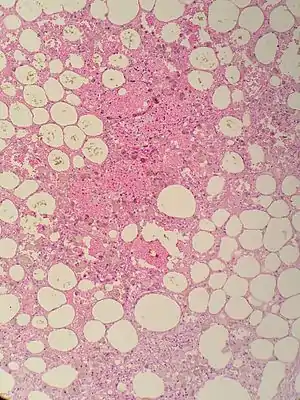

| Sclerosing mesenteritis - note the hemosiderin, chronic inflammation | |

The disorder is identified by histopathology showing fat necrosis, fibrosis and chronic inflammation of the small intestine. Examination of the mesentery may indicate a solitary mass, but diffuse mesentery thickening is common.[4][6]